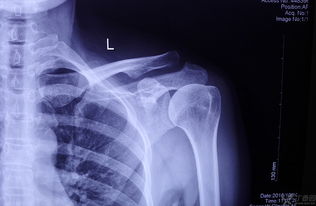

2.手術(shù)療法對肩鎖關(guān)節(jié)全脫位,即Ⅲ型損傷之病人,因其關(guān)節(jié)囊及肩鎖韌帶、喙鎖韌帶均已斷裂,使肩鎖關(guān)節(jié)完全失去穩(wěn)定,上述外固定效果不滿意,對年齡小于45歲者,應(yīng)手術(shù)修復(fù)。

常用的手術(shù)方法有肩鎖關(guān)節(jié)切開復(fù)位內(nèi)固定術(shù)、喙鎖韌帶重建或固定術(shù)、鎖骨外端切除術(shù)、肌肉動力重建術(shù)等。

(3) 第三型:應(yīng)手術(shù)治療,有兩種手術(shù)方法比較常見,即切開復(fù)位與張力帶法固定、再加做鎖骨-喙突拉力螺釘固定術(shù)。